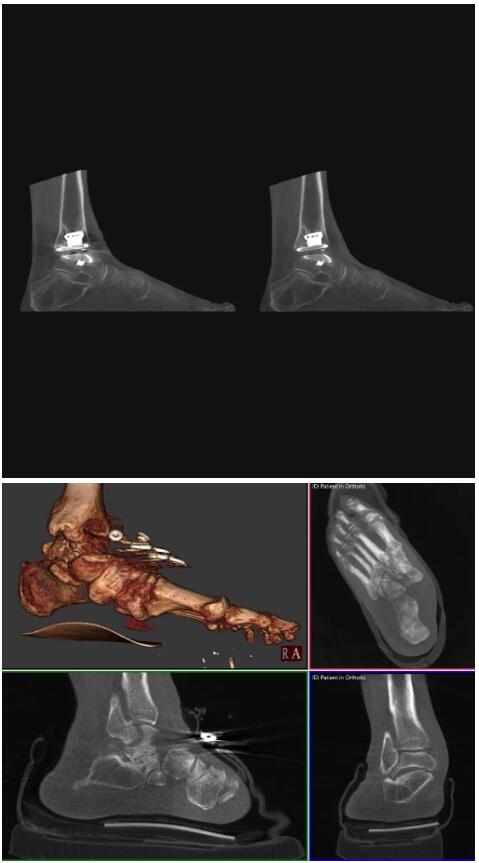

以下是這些“特立獨行”的CT所拍出來的圖像:

而患者站著做足部或者踝部做CT檢查還有個好處是,可以檢查患者在負(fù)重的情況下,骨關(guān)節(jié)的真實情況,而躺著做CT掃查時未必能看出來。負(fù)重CT掃查特別是對于受傷的運動員或者舞蹈員來說意義更大,能夠更準(zhǔn)確地評估傷情,幫助他們盡早復(fù)原。

以上介紹的CT均來自國外同一家公司,這些CT均配置了可視化軟件,可以進行切片、3D重建以及大型CT附帶的所有典型的操作功能。